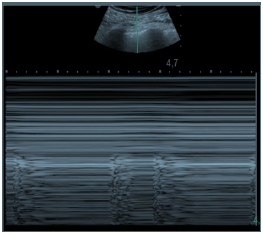

Considere que a imagem apresentada refere-se a um paciente de 40 anos de idade, que se encontra na UTI em VM, com parâmetros ideais para mensuração do delta PP ajustados para VC = 8ml/kg (paciente curarizado). No caso, o monitor multiparamétrico mostra as medidas realizadas.

Antes da mensuração do referido delta PP, foram coletados gasometrias pareadas para o cálculo da saturação venosa central de O2 e do gap de CO2.

Qual par de valores seria compatível com o caso apresentado?

Diante do delta PP encontrado, a melhor conduta é

Com base na leitura do monitor multiparamétrico, assinale a alternativa que corresponde ao delta PP para esse paciente.